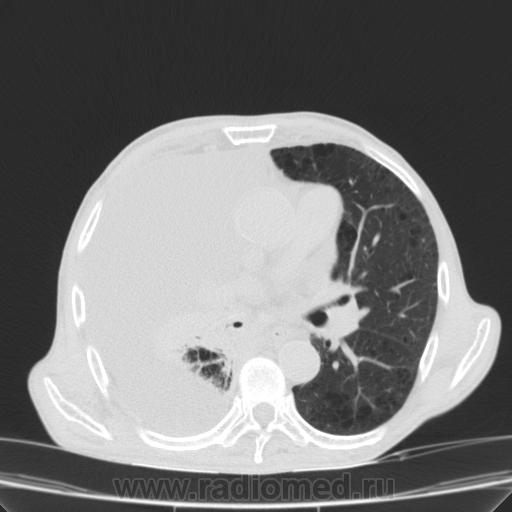

Пожилой мужчина, лечился по н/д правостороннней пневмонии в терап/отделении. Жалобы на одышку, кашель. По результатам Р-контроля после лечения направлен на КТ легких с диагнозом: плеврит справа, распад? В корне правого легкого вижу объёмное образование, с распадом. Смущают размеры плеврита,очень много жидкости, почти до 3 ребра. Анализы крови спокойные- L4,0-6,6, СОЭ 12-16мм. Неужто ТБС, отсев бы был при таком огромном поражении. В посеве мокроты-100% высев клебсиэллы пневмоние. Мокрота на общий анализ в работе-собирает с трудом, изза отсутствия мокроты. Плевральную пункцию еще не проводили. Н азначила бронхоскопию и плеврал пункцию. Как думаете, уважаемые коллеги, это онкопроцесс или тбс распад?

Коллеги, распада там нет, это вас медиастинальное окно подвело. В грудине тоже все в порядке. Да и компрессия позвонка "старая".

Небольшое количество увеличенных лимфоузлов, и те - не сказать, чтоб были очень крупными. От эмпиемы до онкологии... Умеренное количество жидкости в перикарде, толщиной слоя до 13-14 мм. При подобной картине не вижу смысла гадать по сжатому лёгкому, пишу так: массивный выпот справа, около 2500 мл, диафрагма оттеснена жидкостью каудально, печень (!!!) смещена каудально и вправо. Легкое справа значительно компрессировано жидкостью, оценка проходимости бронхов и состояния легочной паренхимы (кроме имеющейся эмфиземы) практически невозможна. Необходима пункция плевральной полости справа (цитология, ВК, посев на микрофлору и проч), КТ-контроль после эвакуации жидкости.